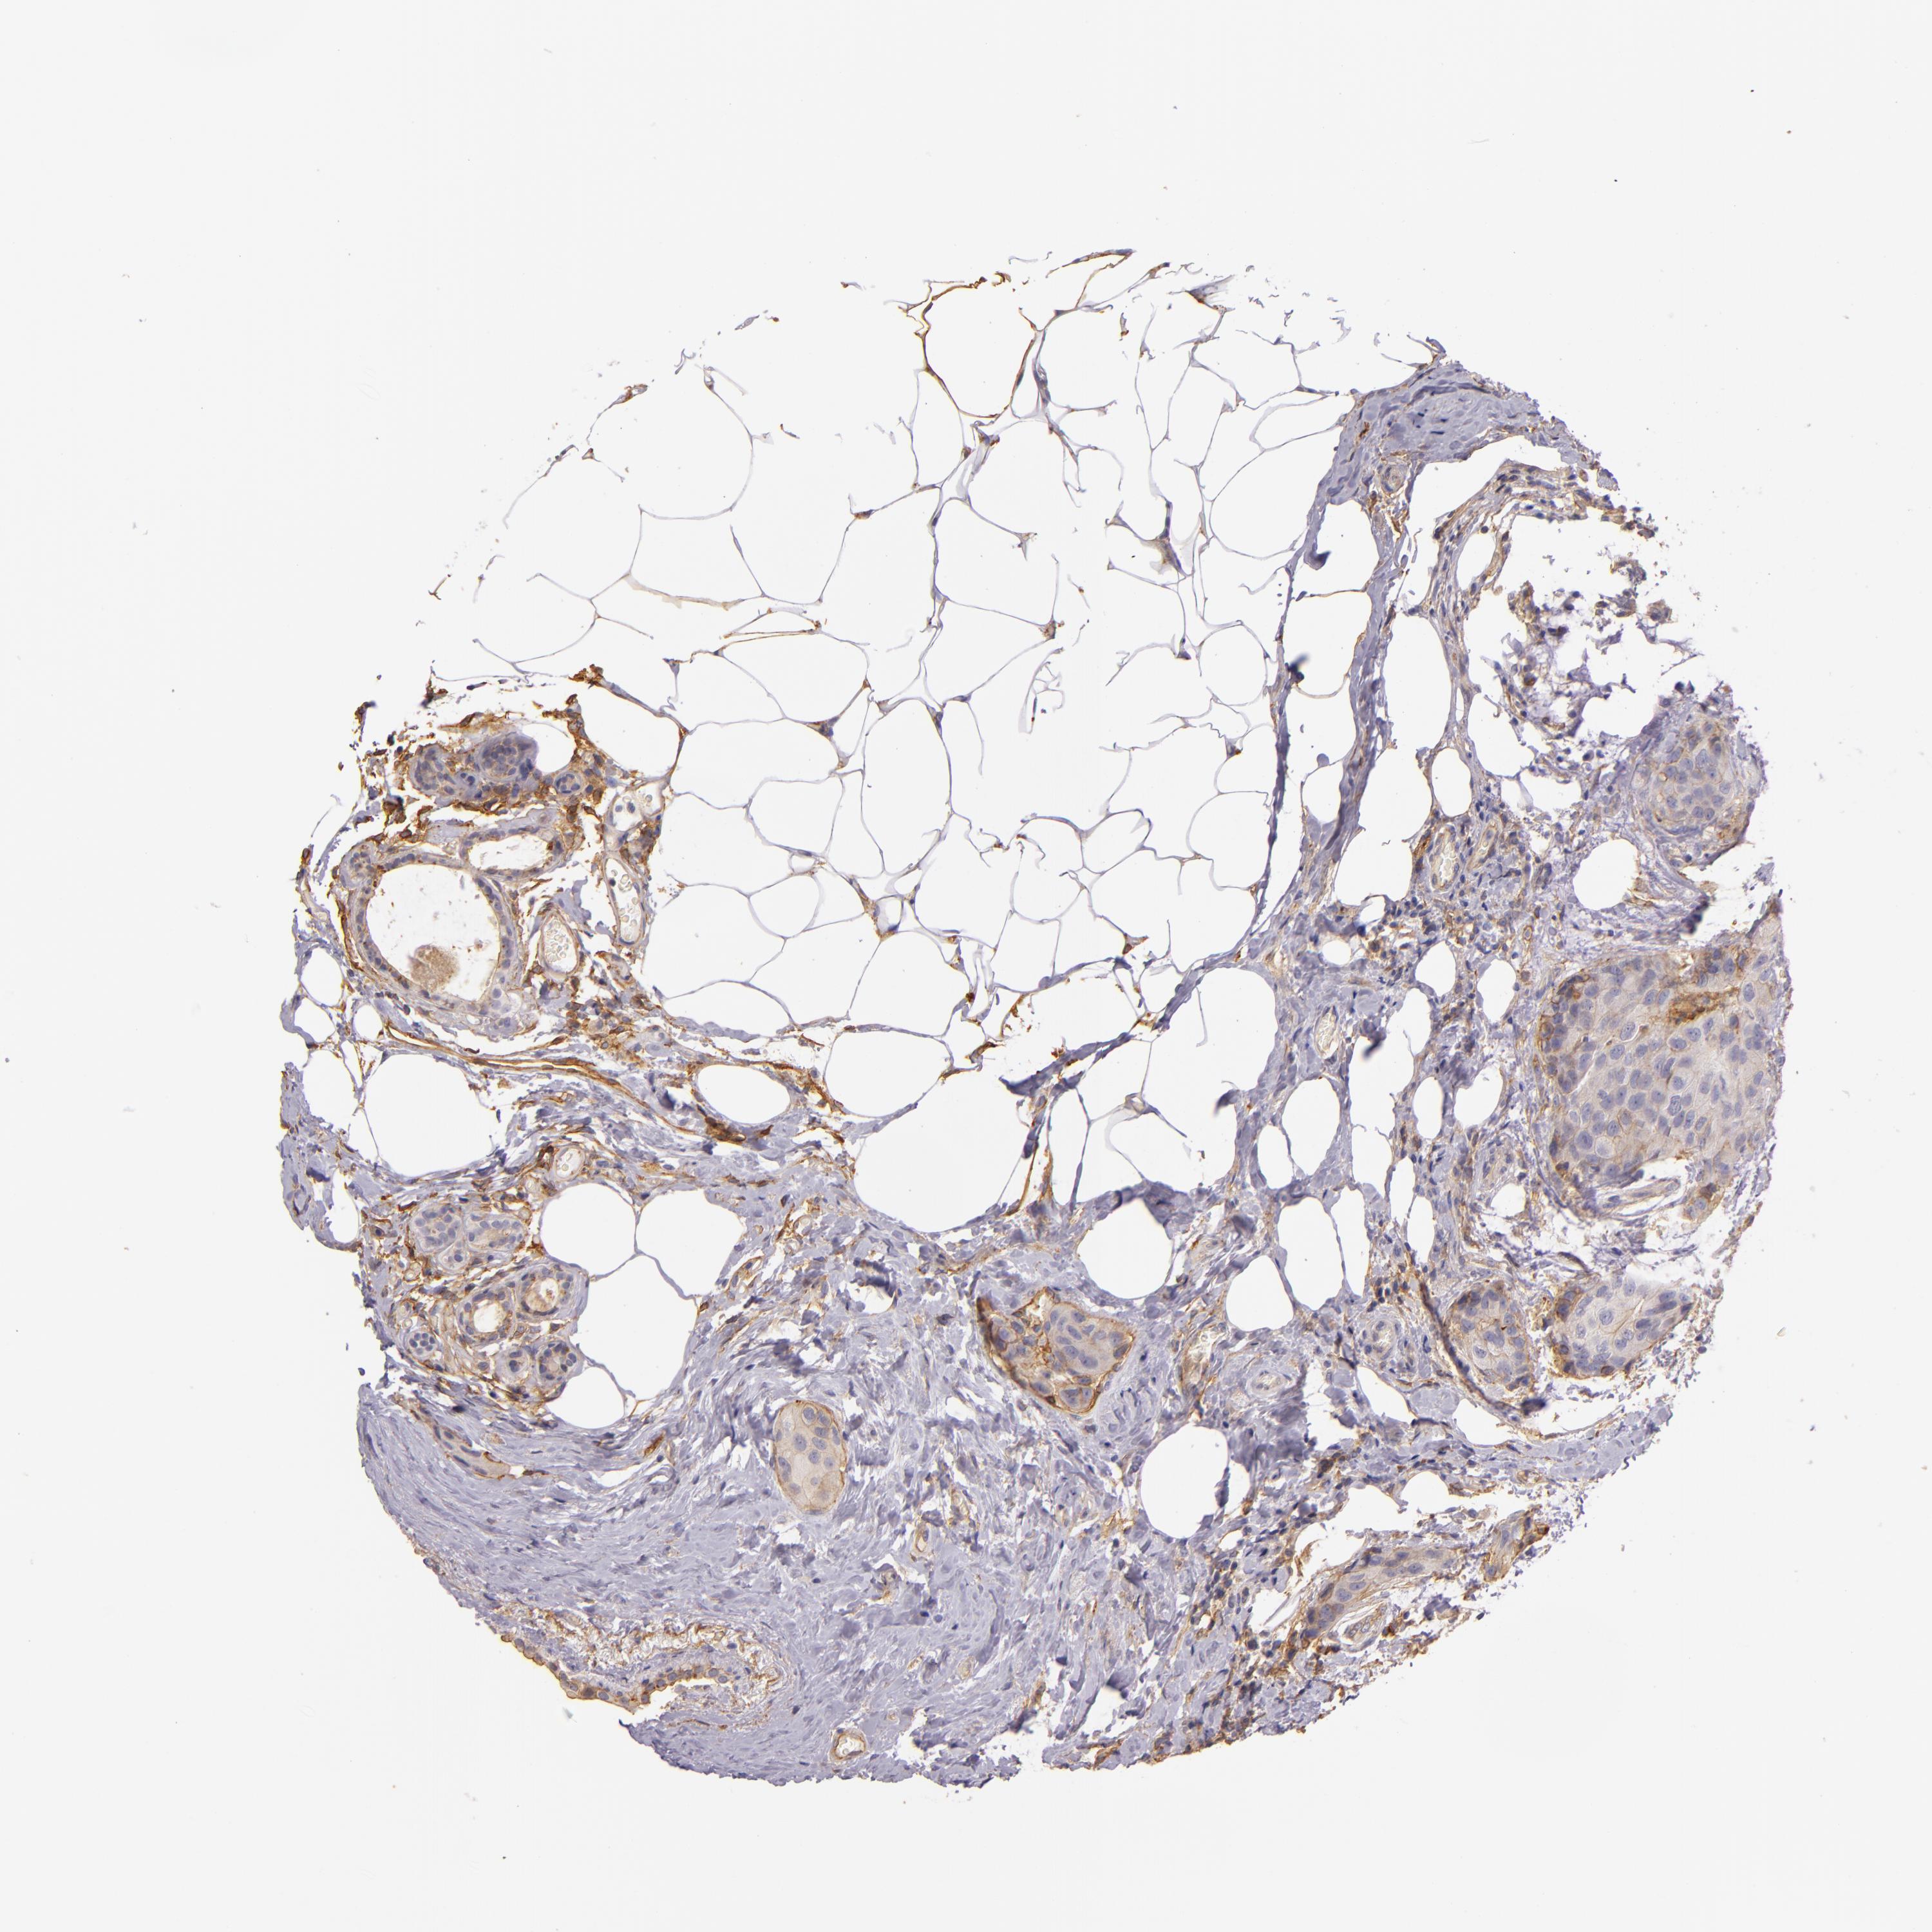

BRCA TCGA BRCA VALIDATION PROTEIN EXPRESSION

Breast cancer

Human cancer